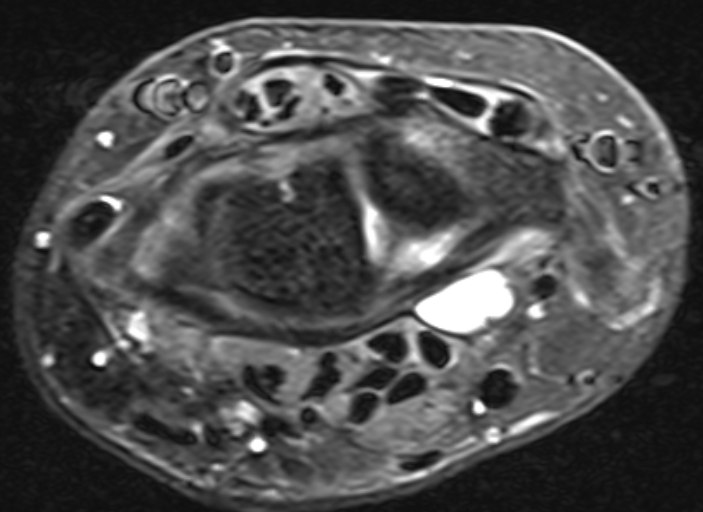

Volar ganglion

Volar ganglion with radial artery superficial to ganglion